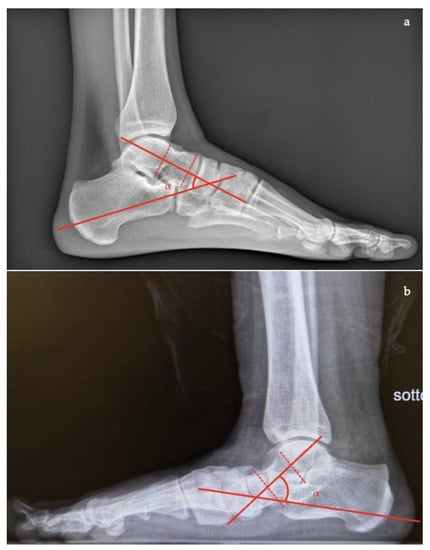

- Talocalcaneal angle is formed by the long axis of the rearfoot and the midtalar line. This angle is increased in pronated feet on both the AP and lateral views (normal <45°, flatfoot >45°) (Figure 7);

- Calcaneal-fifth metatarsal angle, defined as the angle formed between the tangent to the inferior aspect of the calcaneus and a line drawn along the inferior aspect of the base and head of the fifth metatarsal (normal <170°, flatfoot >170°) (Figure 8).